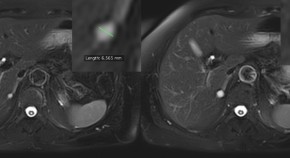

MRI-based structural imaging has become an integral component of the clinical assessment of patients with suspected Alzheimer disease (AD), and atrophy of medial temporal structures is now considered to be a valid diagnostic marker at the mild cognitive impairment stage. In this article, Frisoni et al. consider the roles of structural MRI markers in the diagnosis of AD and non-AD dementias, and in the tracking of disease progression during clinical trials.